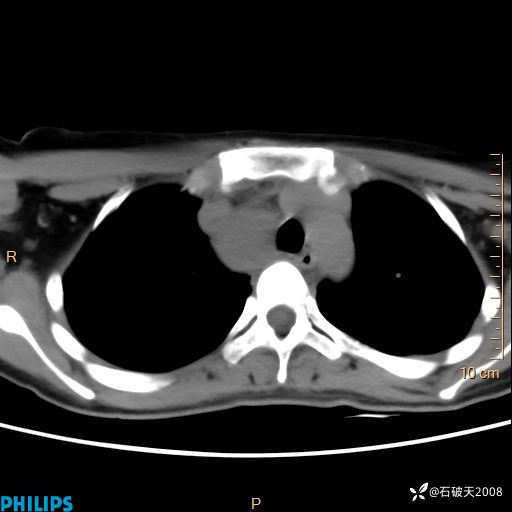

动脉期